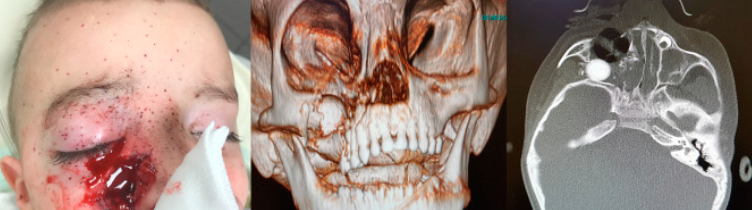

What is your first step in manageing this patient?

What are indications for intubation, trach?

How would you manage haemorrage?

What are the articulations of maxilla, blood supply?

Describe Le Fort I, II, III.

What are the types of palate fracture?